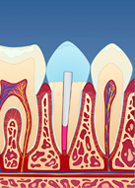

Av og til knekker en tann i nivå med tannkjøttet. Dersom tannen er rotfylt, er det likevel mulig å bygge den opp igjen. Siden det er lite tannsubstans igjen (fig. I), må det først monteres en stift i den rotfylte tannen. Stiftens funksjon er å forankre oppbygningen.

figur I